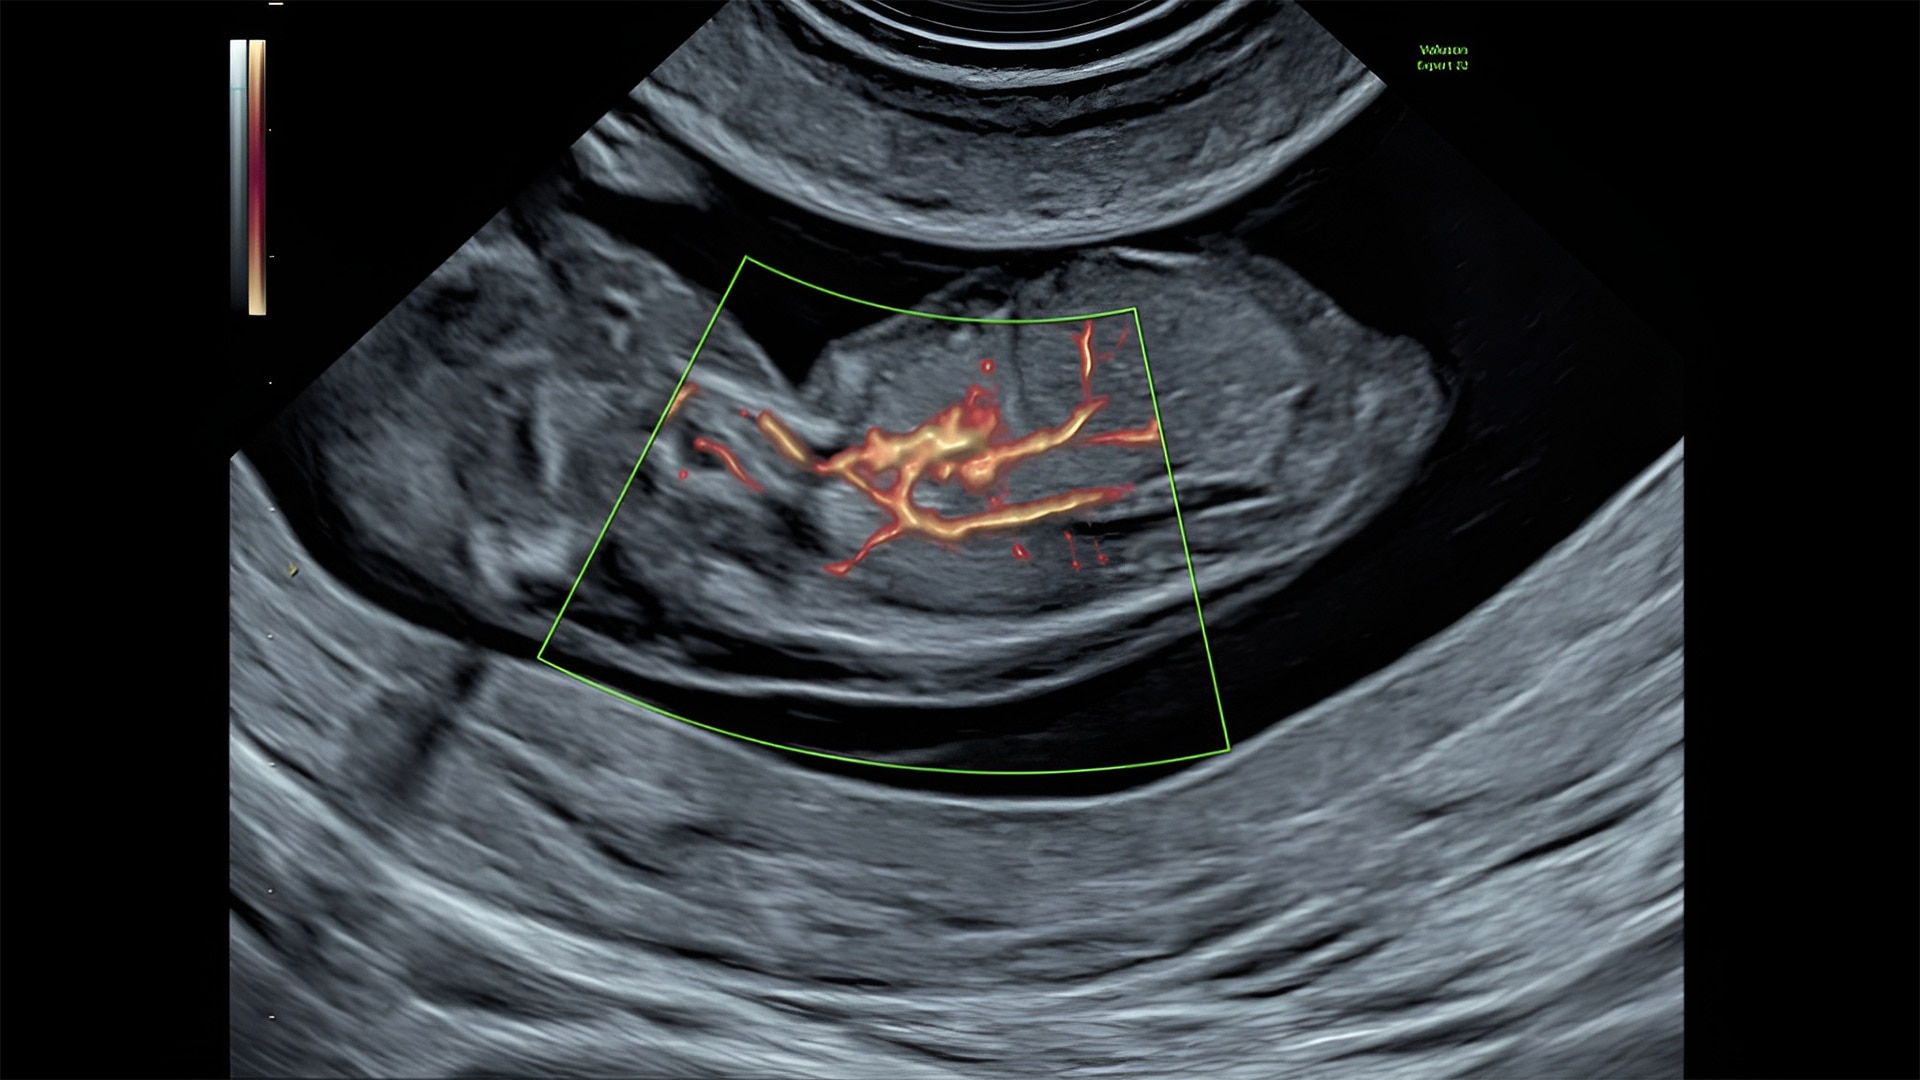

Detect the undetectable

Discover complicated anomalies and pathologies with the Voluson Expert 22 to provide answers sooner for better decision making.

Complex cases come with enough uncertainty. That's why the Voluson Expert 22 is specifically designed for in-depth assessment of complicated anatomy — with pioneering first trimester, fetal cardiac, gynecological, and other pivotal technologies that focus on early detection and intervention.

Identifying fetal cardiac abnormalities earlier means you can intervene sooner, plan for delivery, and potentially improve outcomes. The Voluson Expert 22 provides a full solution of progressive tools, to help distinguish the tiniest structures with stunning clarity to provide patient answers faster.